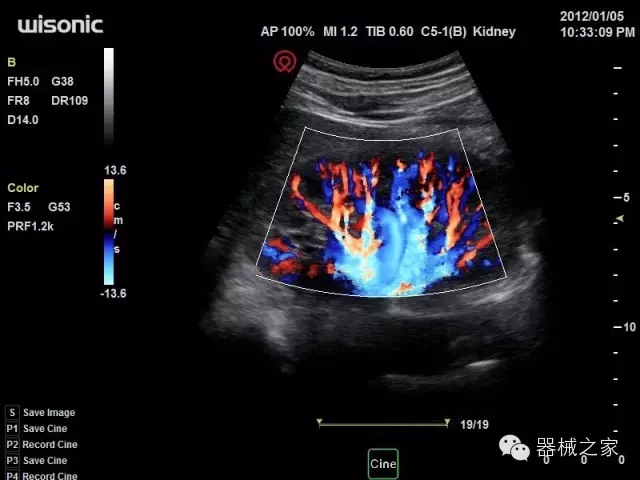

臨床圖片賞析

·全球目前唯一一款配備主機(jī)雙探頭接口,整機(jī)重量(含電池)在5公斤以內(nèi)的便攜式彩超;

·獨(dú)有的HoloTM PW 實(shí)時(shí)3取樣門PW成像技術(shù),精確進(jìn)行血管診斷;

·一鍵優(yōu)化B、Color、PW,Auto Doppler自動(dòng)識(shí)別血管位置、偏轉(zhuǎn)角度等,提高工作效率;